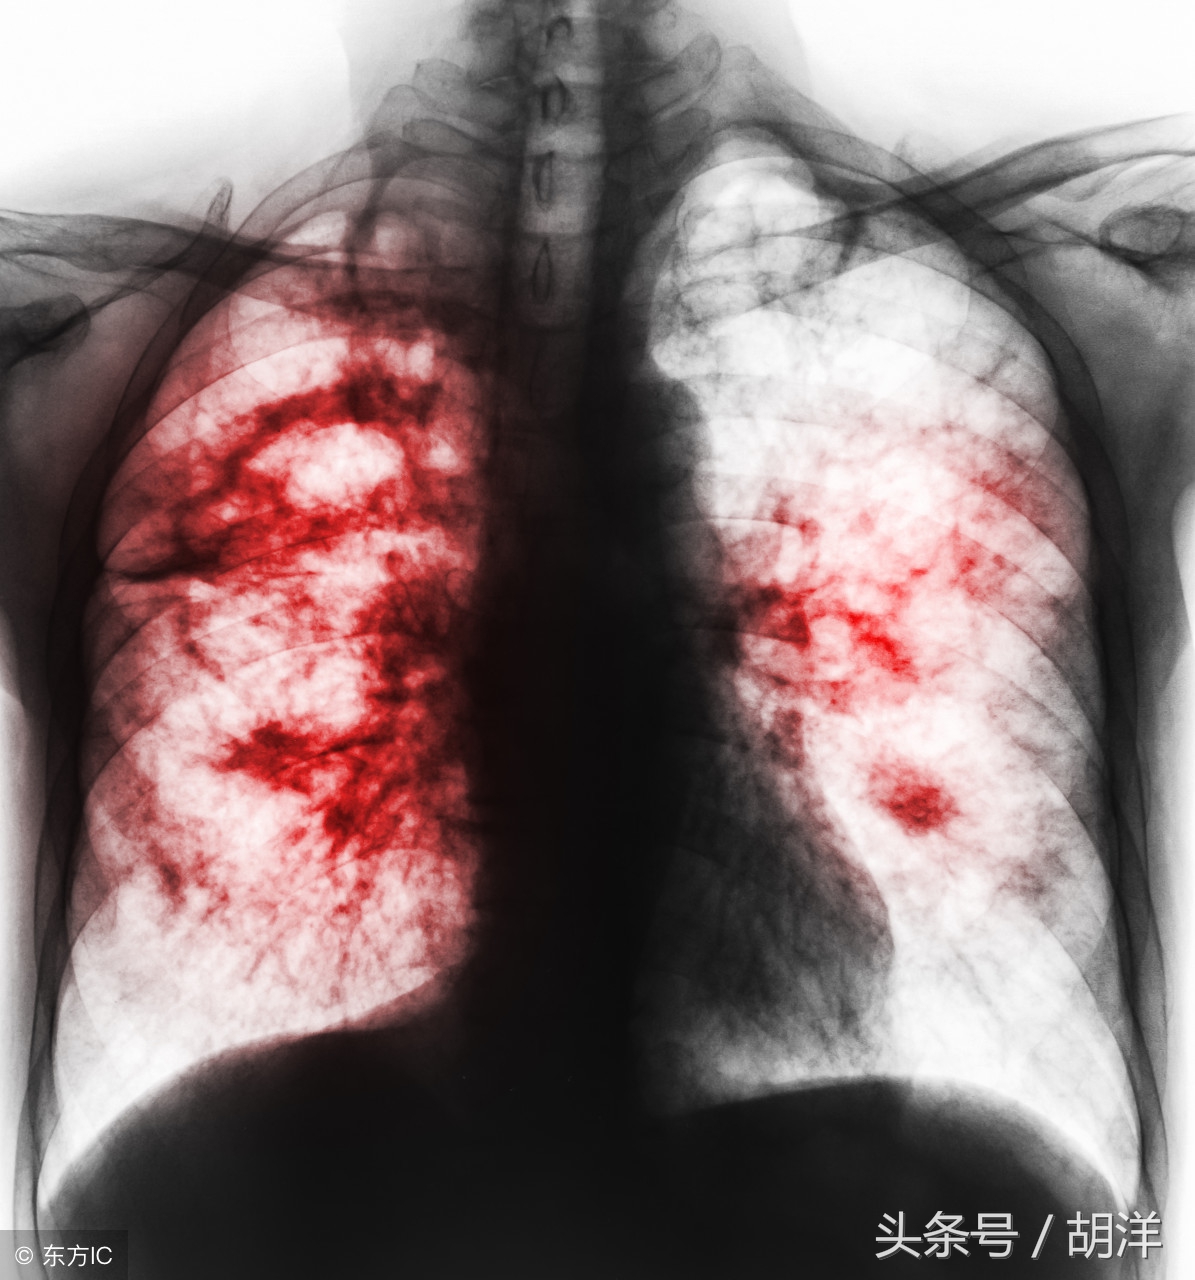

小细胞肺癌在所有肺癌病人中占15-20%,恶性程度高,容易通过血液和淋巴道转移,转移发生早而且广泛。由于小细胞肺癌与其他肺癌有完全不同的特性,因此分期方法有所不同,除了TNM分期,常用美国退伍军人分期标准,分为局限期和广泛期。局限期小细胞肺癌的特点是肿瘤局限于一侧胸腔内,包括有锁骨上或前斜角肌淋巴结转移和同侧胸腔积液。当病变超出局限期范围,均称为广泛期。